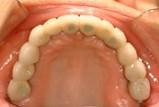

问题 可能造成金属表面崩瓷的是 ( )

选项 A.由于油污等造成金属基底桥架表面污染 B.瓷层厚度不足 C.瓷粉与金属热膨胀系数不匹配 D.预氧化处理时造成氧化层过厚 E.金瓷衔接区位于非咬合接触区

答案 ABCD